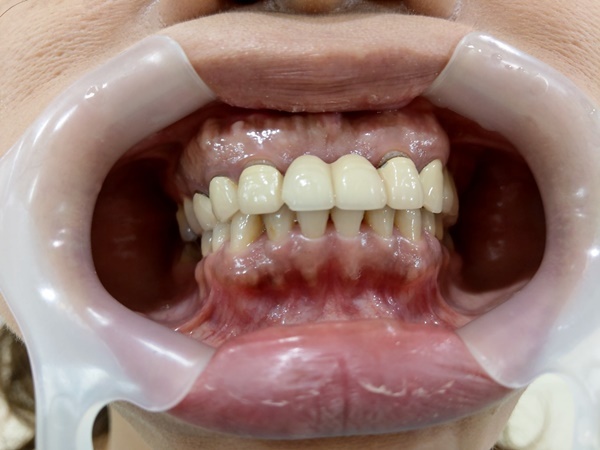

一進到新全美牙醫裡面,空氣是一陣清新,而且不得不說這裡的護士漂亮又貼心,妹妹也沒少含蓄,平時不是還很大喇喇嗎?哈哈,不只幫妳拿拖鞋,照牙齒照片還會很貼心幫妳穿背心,男士們是不是很動心呀!

後來貼心小護士走來告訴我妹妹快好了,讓我去看看我一進去雖然差點嚇死…可是為了幫妹妹紀錄,我還是勇敢的拍下這張(死小瑜妳欠我一次…),為了不造成大家看文暈倒情況,我碼到剩縫線了…大致上就是把妳的牙肉切開就是傳說中翻瓣植牙手術,然後把植體種進去,在把傷口縫起來。怕了嗎…?告誡大家除了無法預知意外,不然一定要顧好牙齒啊…

說實在我也不好受,植牙是需要恢復期三到六個月,尤其是上面牙齒,恢復期會比下面長一點,至少六個月以上,主要是因為上排骨頭比起下排牙骨還來的薄,恢復後還要再來回診一兩次,最後完全癒合才會給正式假牙,戴習慣之後醫師就會幫患者固定,才有大家現在看起來這麼自然健康的牙齒。剛植完植體還是要好好保養喔,聽楊醫師說如果植牙後回去沒有好好保養,中途可是很容易發炎,到時候就要再次回診去給醫師檢查,嚴重可能要再清除一次,所以來植牙的各位無論是微創植牙、翻瓣植牙,也一定要繼續保養口腔,不然會很可怕。